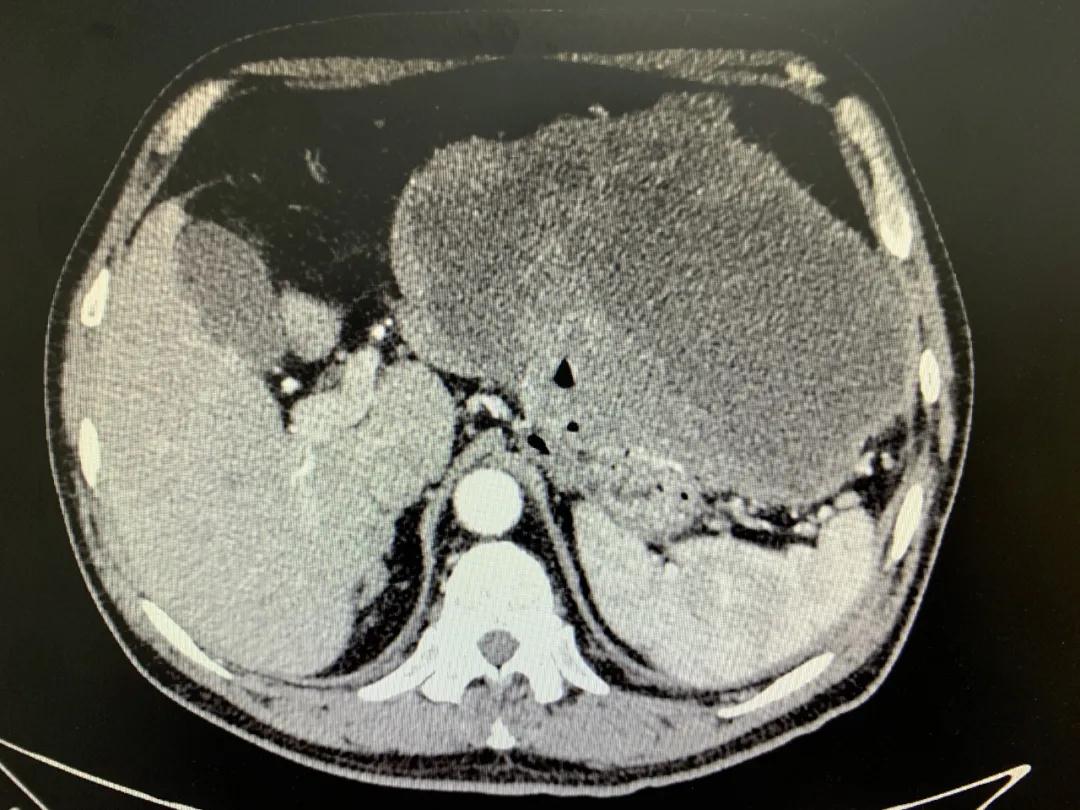

患者入院時血紅蛋白數(shù)值仍持續(xù)下降,出現(xiàn)失血性休克表現(xiàn),危及生命。消化外科二病區(qū)蔡磊主任接診后,組織科室迅速對患者進行了全面的檢查。CT提示腫瘤大小約19.3*10.3cm,腫瘤內(nèi)提示大量積血。結(jié)合相關(guān)檢查,考慮為罕見的巨大胃間質(zhì)瘤合并出血。

蔡磊主任團隊立即為患者安排了手術(shù),術(shù)中發(fā)現(xiàn)腫瘤巨大,占據(jù)大部分胃壁,胃腔內(nèi)殘存血液達3400ml之多,且多為新鮮活動性出血,給手術(shù)增加了非常大的難度。但蔡磊主任團隊克服困難,在麻醉手術(shù)中心的幫助下,終于將腫瘤完整切除,術(shù)后稱量腫瘤達10斤重!